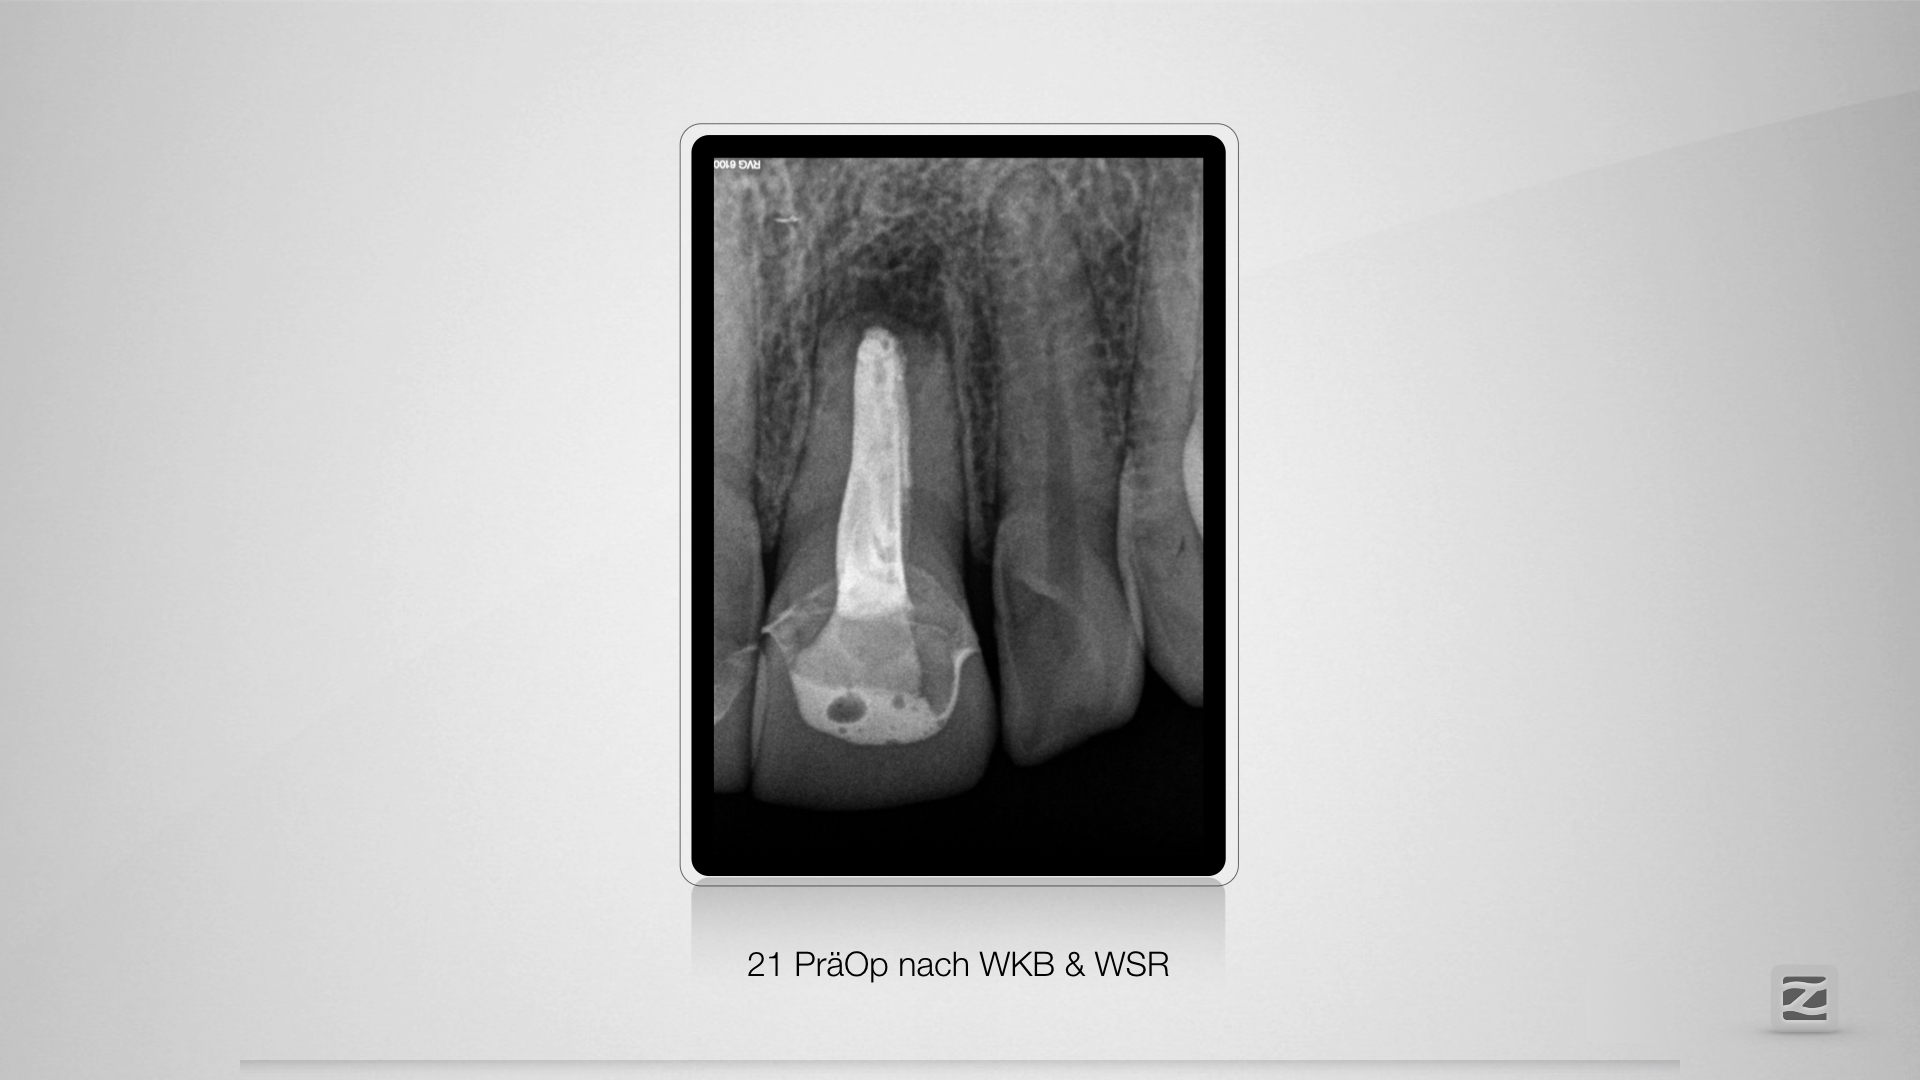

21D.001

Der Schein trog!